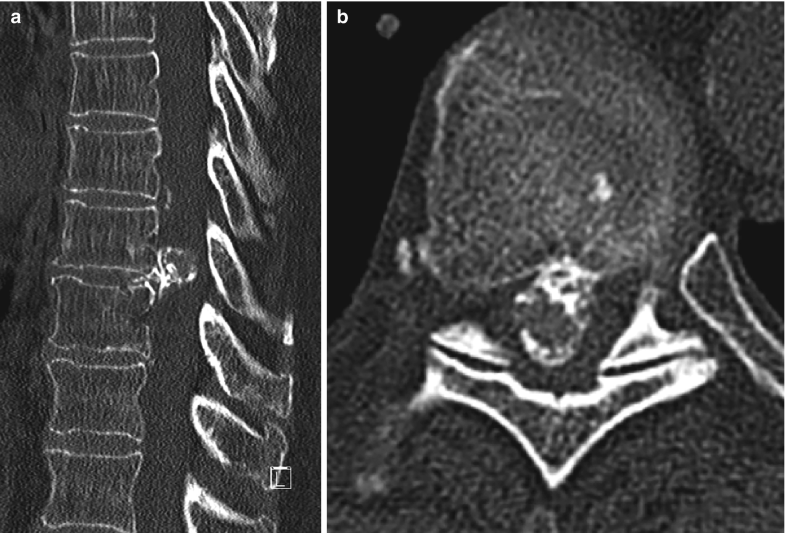

Typical case 1. A 35‐year‐old male patient with myelopathy caused by Disc Herniation Myelopathy Symptoms Degenerative cervical myelopathy is a condition that is caused by age related changes to the bones, ligaments and discs of. Spinal compression from overgrown bone or ligaments, disc herniation, intrinsic and. When the discs between the vertebrae bulge or break, pressing on the spinal cord. Typical symptoms for each include: There are many possible causes of myelopathy: Thoracic myelopathy causes. Disc Herniation Myelopathy Symptoms.